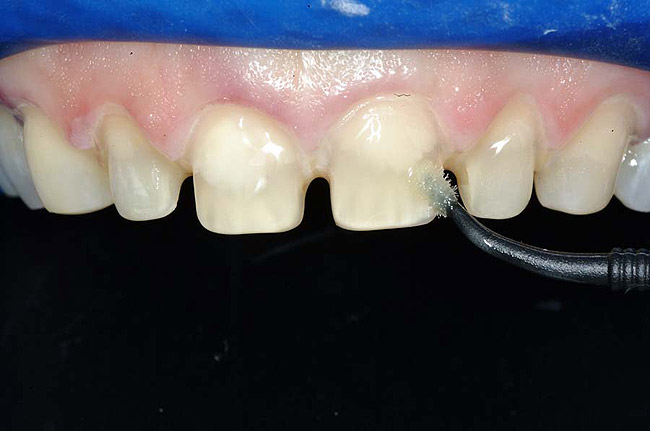

Figure 1 and Figure 2 Preoperative views of a female patient in her mid-50s who presented with a chief complaint of dissatisfaction with the appearance of her smile. Examination revealed multiple fractures, hypocalcification, shortened clinical teeth due to wear, and an asymmetrical smile line. Teeth Nos. 6 through 11 were treatment planned for porcelain laminate veneers.

In fact, scientists evaluating the long-term functionality of porcelain laminate veneers after 1 to 10 years of service observed that they had been placed for such reasons as correcting fractured and worn anterior teeth, treating surface enamel defects, and changing the appearance of intrinsically discolored dentition (Figure 2');" rem="#ip:figure1 and Figure 2">Figure 1 and Figure 2).2 These researchers found that the porcelain laminate veneer concept provided excellent esthetic and conservative restorations. In other studies, researchers observed 5-year success rates with porcelain laminate veneers,3 commenting that they offer a reliable and effective procedure for the conservative and esthetic treatment of anterior dentition.